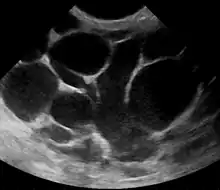

An ultrasound image of puerperal mastitis

Puerperal mastitis is the inflammation of the breast in connection with pregnancy, breastfeeding or weaning. Since one of the most prominent symptoms is tension and engorgement of the breast, it is thought to be caused by blocked milk ducts or milk excess. It is relatively common; estimates range depending on methodology between 5–33%. However, only about 0.4–0.5% of breastfeeding mothers develop an abscess.[7]

Risk factors include poor latch, cracked nipples, use of a breast pump, and weaning.[1] The bacteria most commonly involved are Staphylococcus and Streptococci.[1] Diagnosis is typically based on symptoms.[2] Ultrasound may be useful for detecting a potential abscess.[1]

However, if the doctor is not sure whether the mass is an abscess or a tumor, a breast ultrasound may be performed. The ultrasound provides a clear image of the breast tissue and may be helpful in distinguishing between simple mastitis and abscess or in diagnosing an abscess deep in the breast. The test consists of placing an ultrasound probe over the breast.